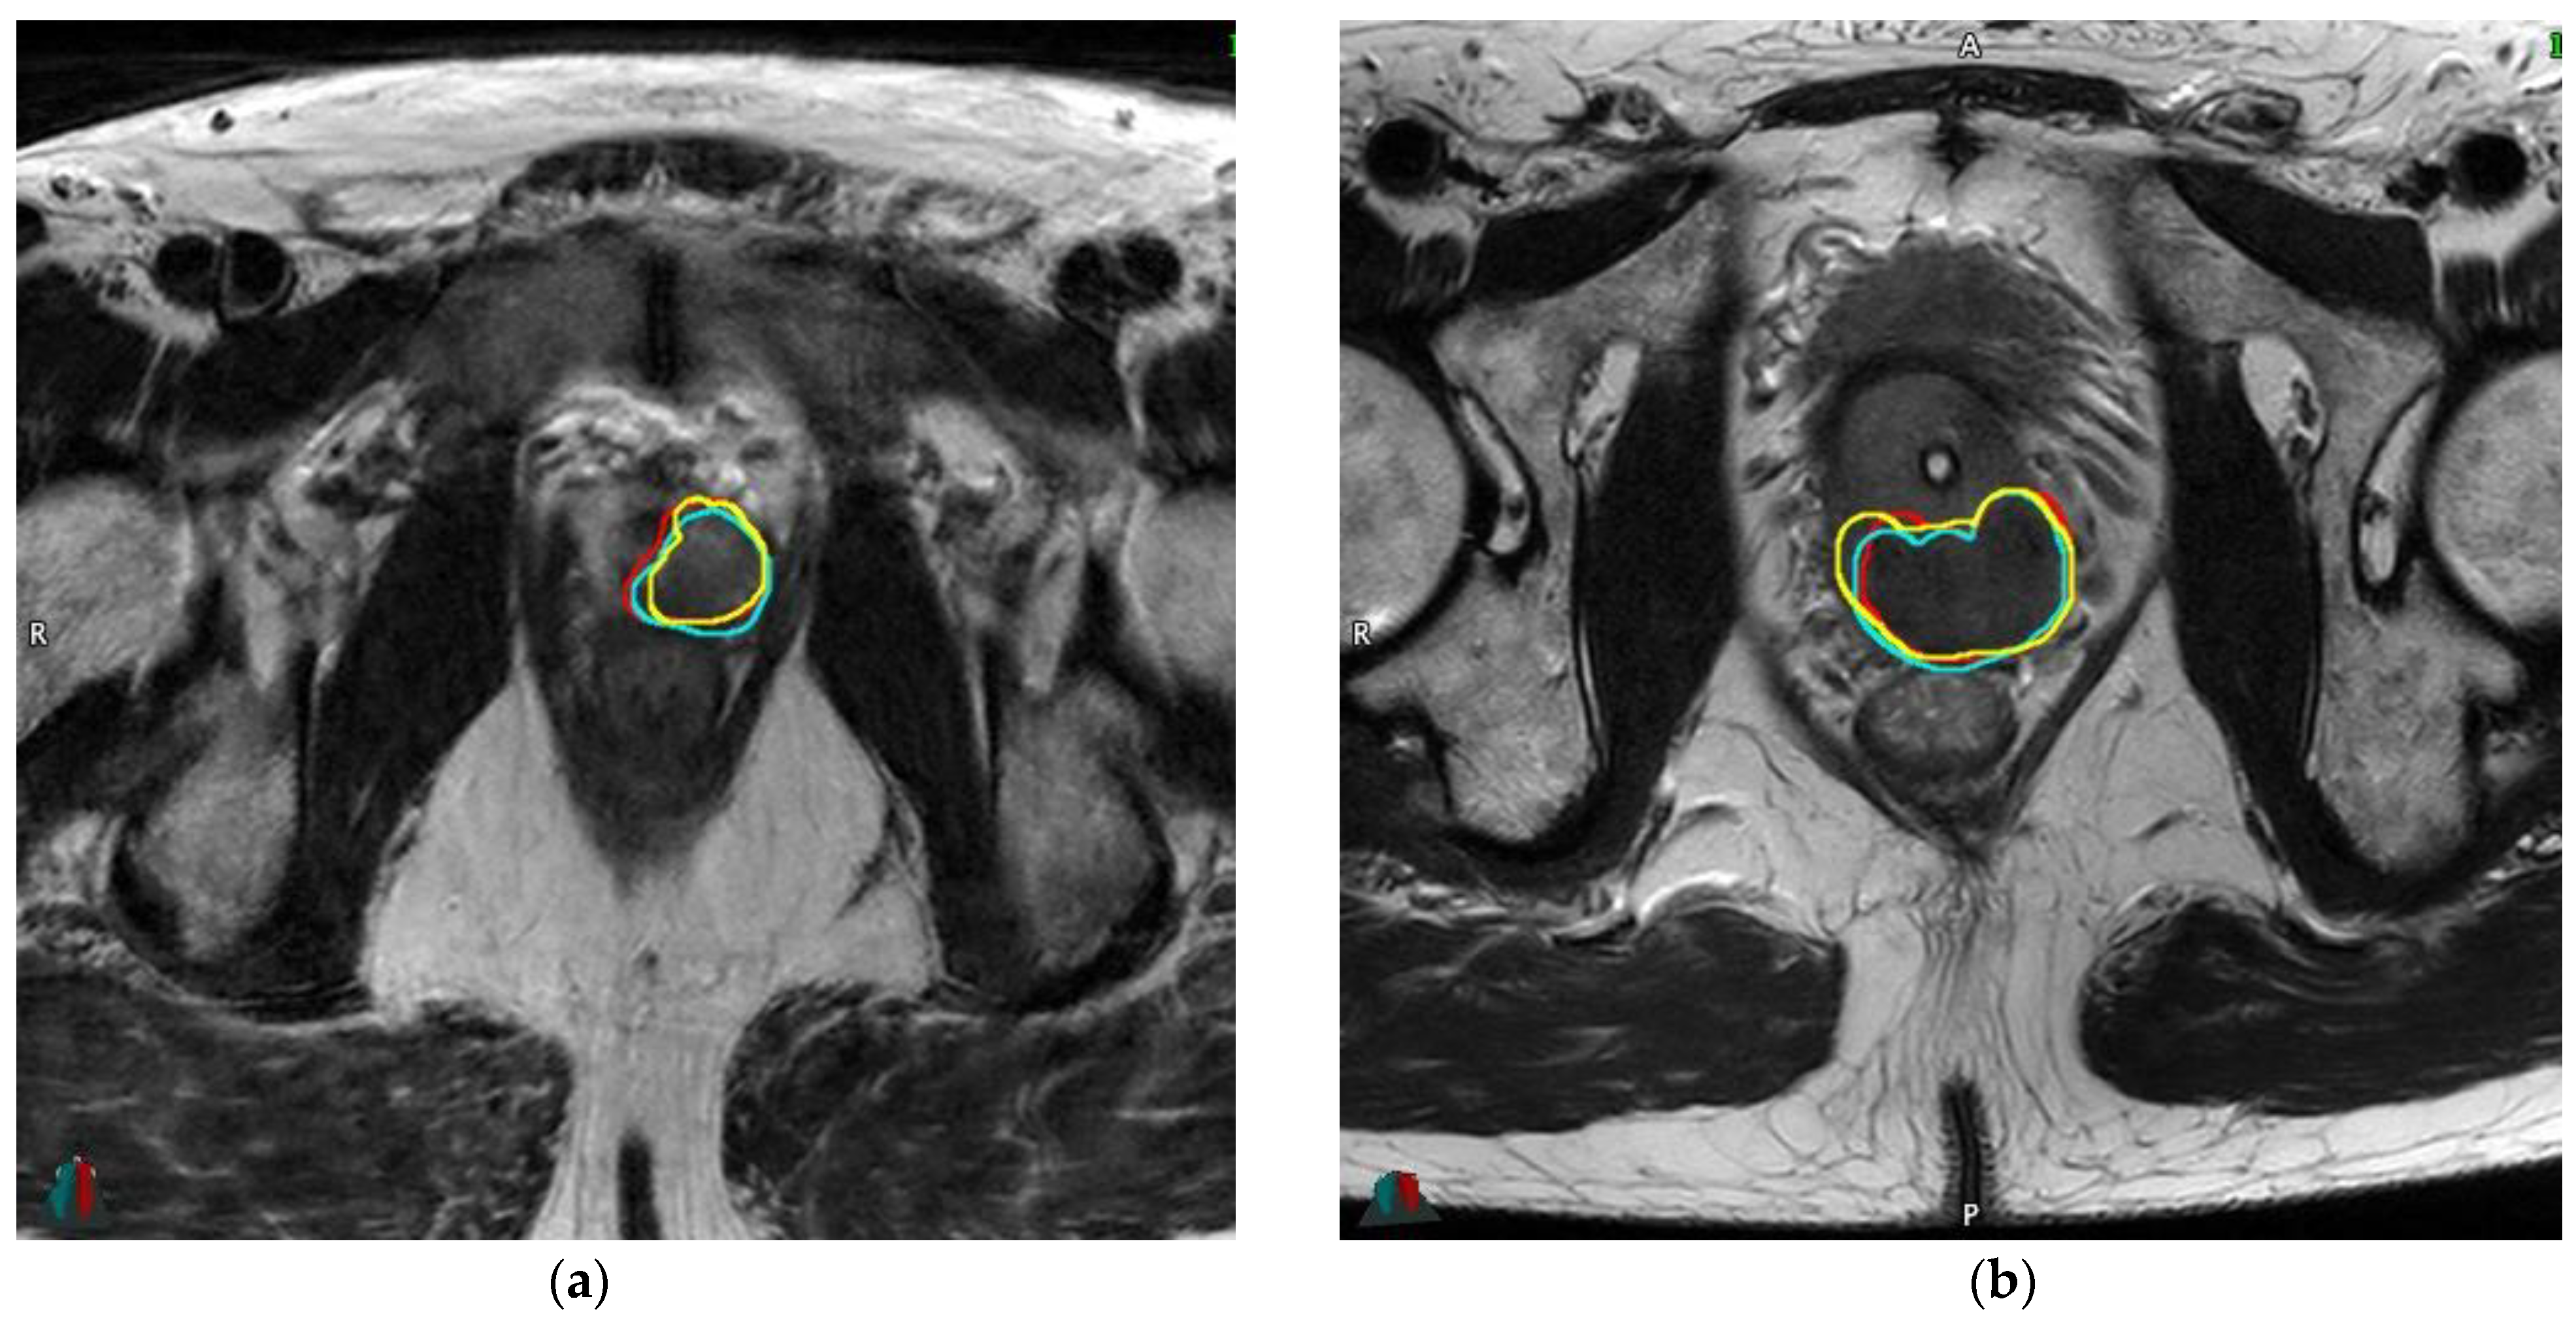

2.2. Prostate MRI

2.5. Inter-Reader Variability

3.5. Inter-Reader Variability